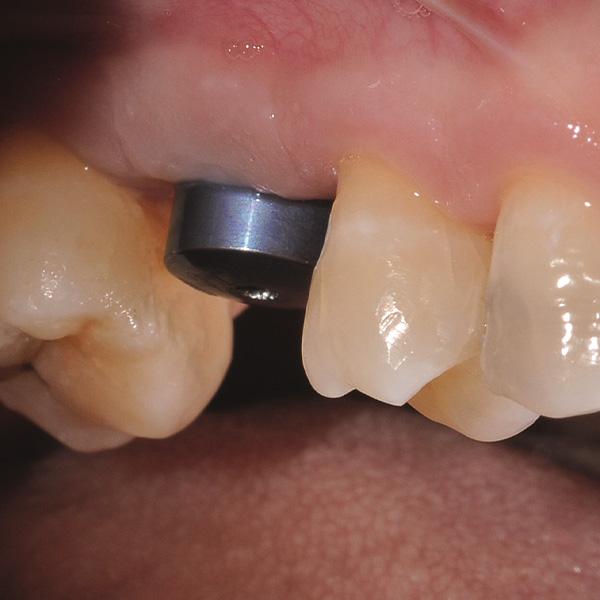

Restauri supportati da impianti sono soggetti a carichi particolarmente elevati. Dopo l‘estrazione e l‘impianto al paziente manca l‘apparato di fibre elastiche del letto dentale naturale. Per questo motivo le forze di masticazione non vengono assorbite, ma trasmesse direttamente sul restauro, l‘impianto, l‘osso e la dentatura antagonista. La ceramica ibrida VITA ENAMIC ha una struttura a reticolo duale in ceramica (86 % in peso) e polimero (14 in peso). Ne risulta un‘elasticità simile alla dentina e la capacità do assorbire le forze di masticazione. Il blocchetto policromo VITA ENAMIC multiColor in geometria EMC-16, grazie alla sua elevata dimensione verticale, consente di realizzare corone-abutment monoblocco, monolitiche anche nel caso di osso atrofizzato. L‘odontoiatra Professor Dr. Alexander Hassel mostra in questo contributo come riabilita una paziente con questa forma di restauro.